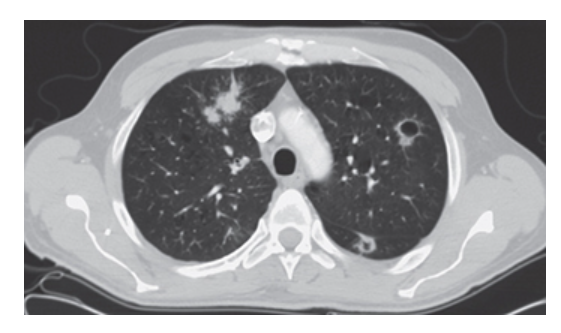

Bronchogenic Carcinoma. CT of the chest with lung windows shows bilateral round pulmonary nodules with irregular speculated margins.